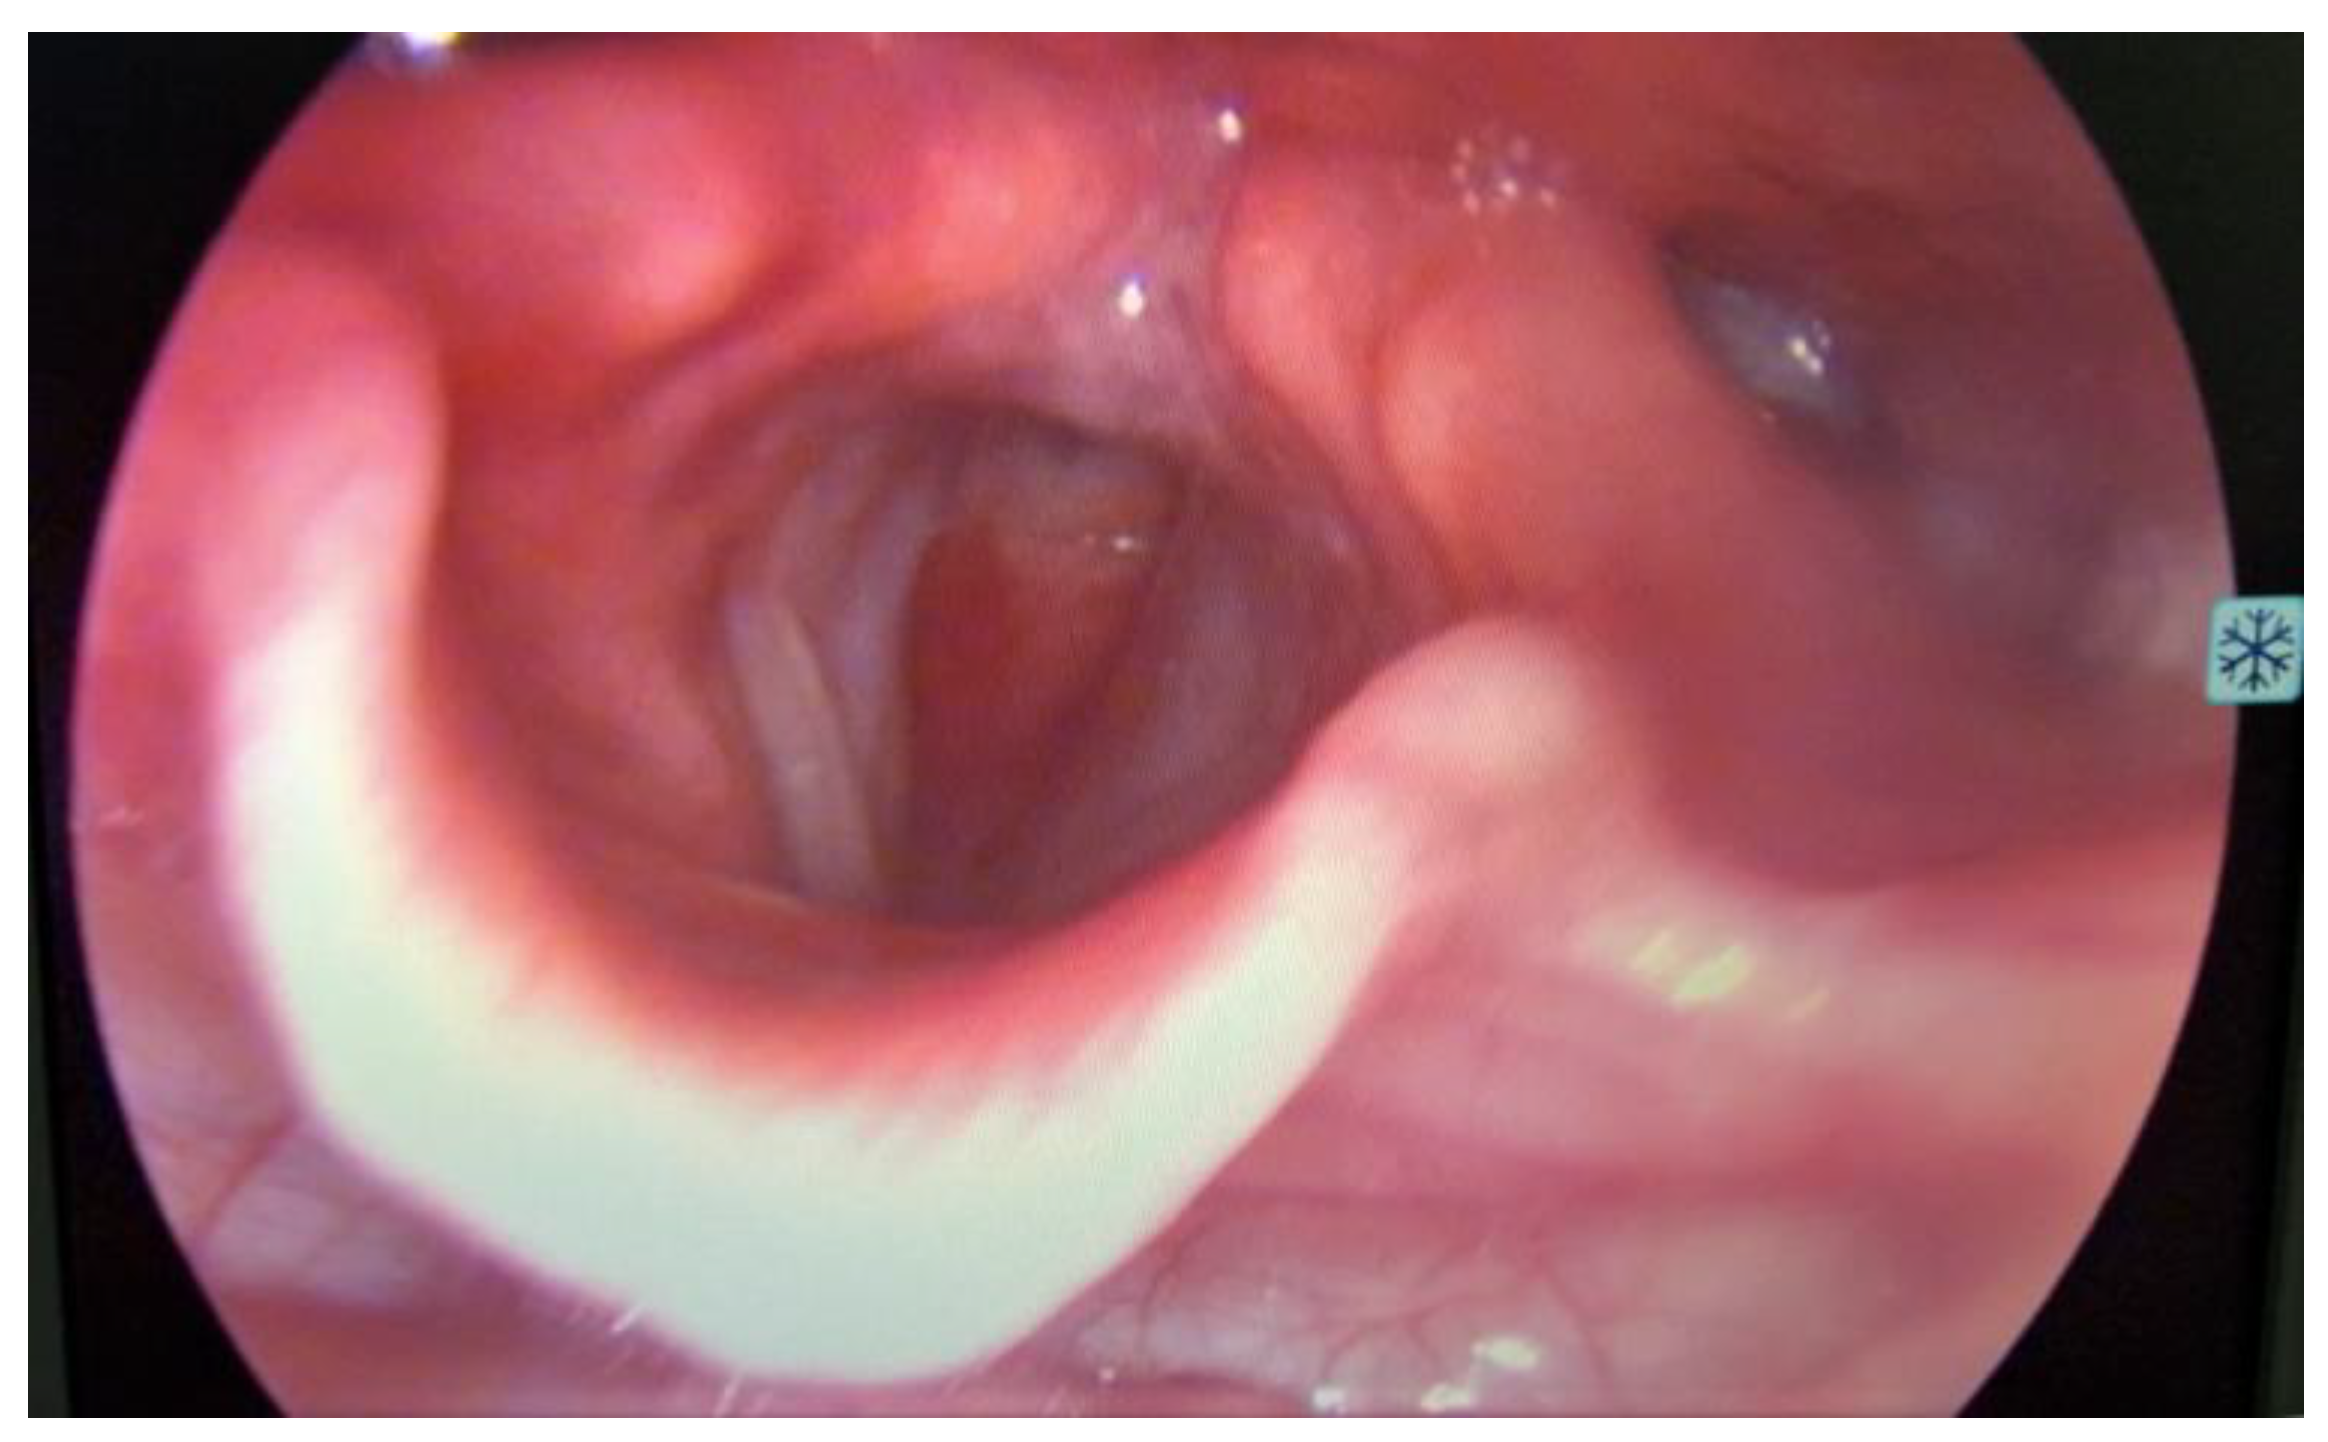

On ORL (Otorhinolaryngology) examination, the patient was in severe respiratory distress, with tachypnea, use of accessory muscles, and showing no lymph nodes or masses at visual inspection and palpation of the neck. At laryngoscopy (Figure 1), supraglottic areas showed a normal appearance, free vocal cords, with preserved mobility, and a subglottic tumor formation located at the level of the first tracheal ring, with marked narrowing of the respiratory space.

Figure 1.

Laryngoscopy revealed a bulging subglottic mass, without visualization of the first tracheal ring, with marked narrowing of the respiratory space, normal appearing supraglottic and glottic area.